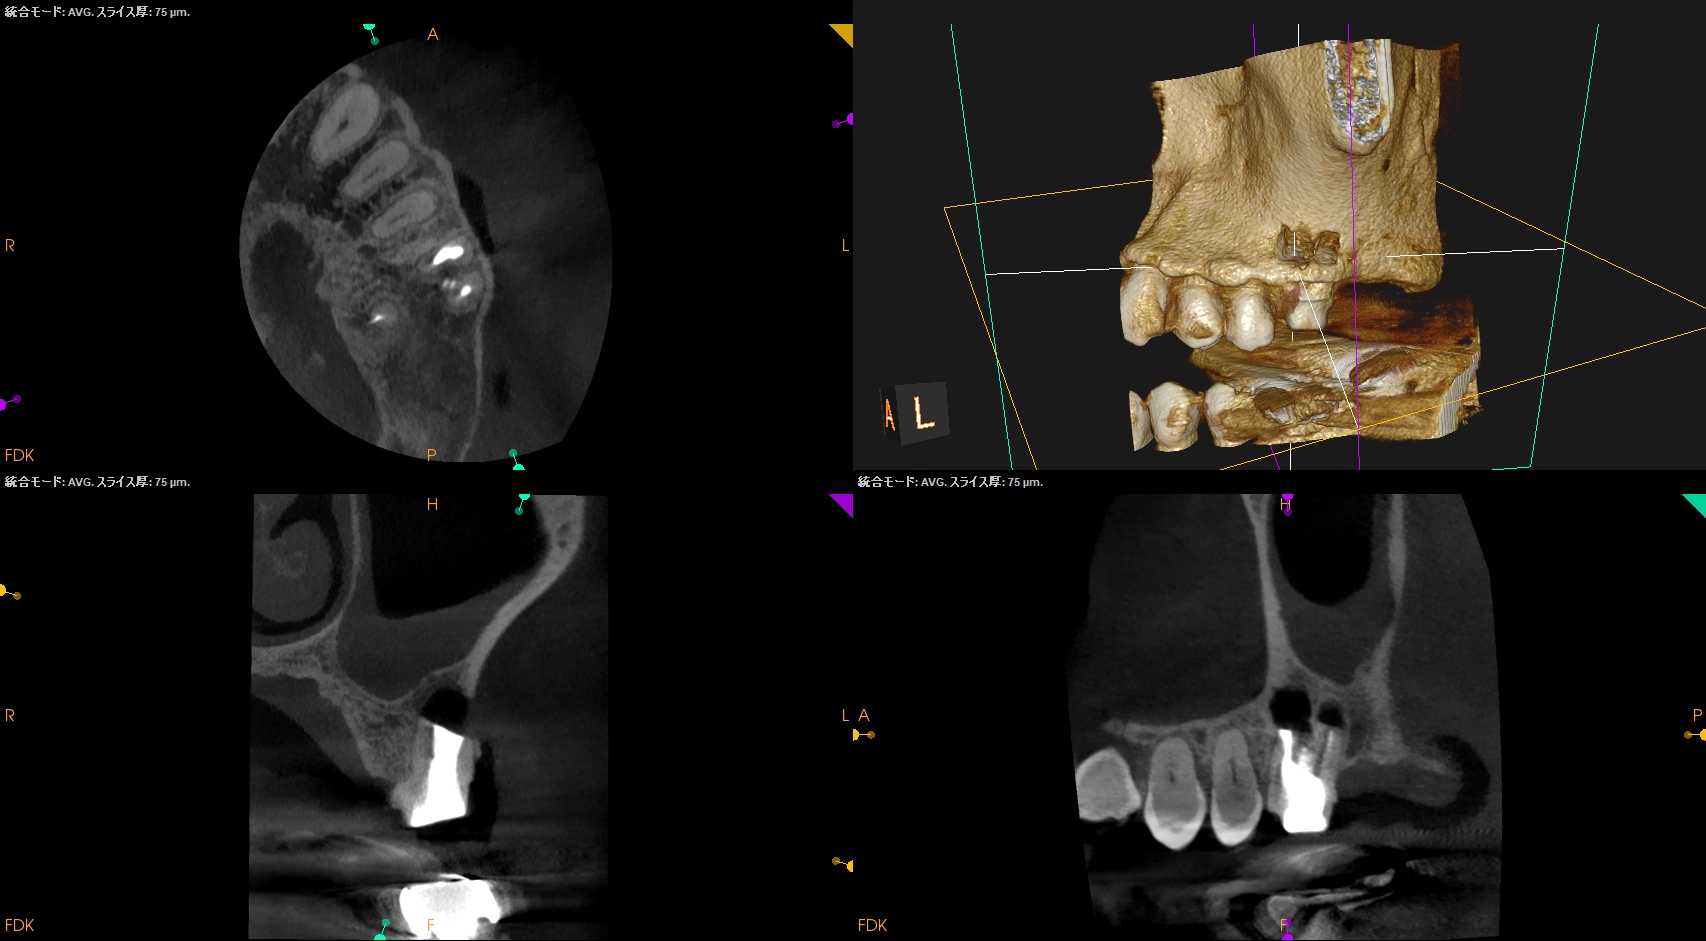

#14 MB+DB Apicoectomy(2026.2.10)

CBCTを参考にCEJよりDBのApexを測定し該当部位をOsteotomyし、Root resectionし、メチレンブルーで染色した。

この際の断面が上記のCBCTの絵に掃除であれば問題ないが、切り残し(アゴ)が残存したので切断し直している。

DBを逆根管形成し、逆根管充填した。

術後にPA, CBCTを撮影した。

MB

DB

問題はないだろう。